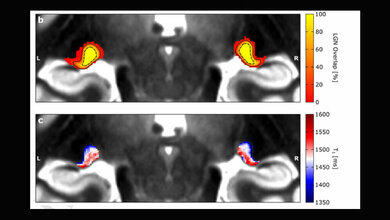

Alle 110 Patientinnen und Patienten, die an dieser Studie teilnahmen, erlitten ein Schleudertrauma mit leichten traumatischen Gehirnverletzungen nach einem Autounfall. Sie unterzogen sich fünf Tage später einer funktionellen MRT, wodurch die Forschenden Hippocampus und Kortex sowie deren Kommunikation untereinander beobachten konnten. Der Beobachtungszeitraum betrag ein Jahr zur Messung der Schmerzintensität und zur Beobachtung, welche Patientinnen und Patienten chronische Schmerzen entwickelten und welche nicht.

Das Ergebnis zeigte eine deutliche Verbindung zwischen der Entwicklung chronischer Schmerzen und der Reorganisation des hippocampalen Netzwerks. Bei Patientinnen und Patienten mit chronischen Schmerzen auch noch ein Jahr nach dem Autounfall zeigen eine verstärkte Verbindung zwischen Hippocampus und dem posterioren Netzwerk sowie letzterem und der Amygdala. Diese mit Angst assoziierte Verbindung nahm zu im Zeitraum zwischen Verletzung und MRT.